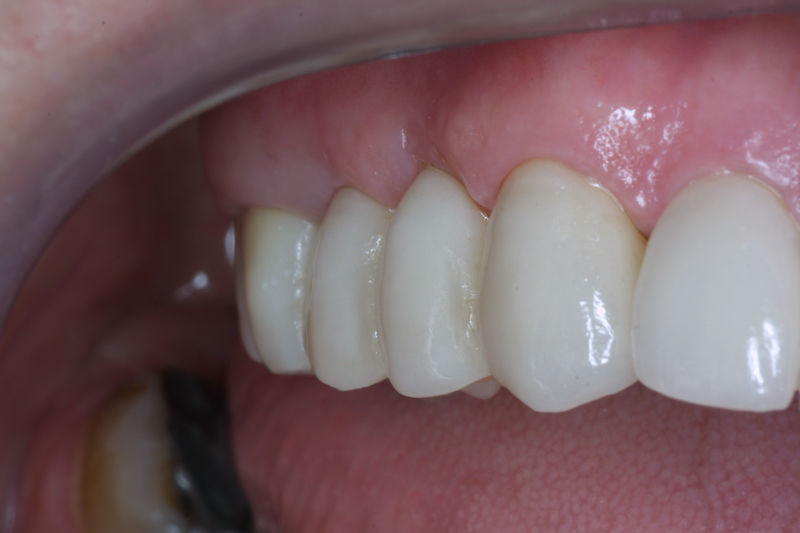

Implantes, ortodoncia y coronas.